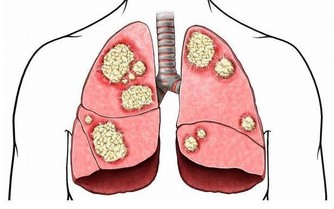

而維他命C片更爛,婦女們服用它的目的是想皮膚美白,但是結果是多服維他命C片會支持乳癌細胞的成長,其他不勝枚舉。

而且由於長期未治好,終於把食道燒傷,結果就是食道癌、胃癌或淋巴癌或胰臟癌。

乳癌就是一種壓制不住的糜爛,其末期非常的惡臭,曾有此類病患到我診所,結果此惡臭在室內連續一星期才散去。

女人會得到乳癌的原因90%是每年去西醫那做乳房健康檢查造成的。

另外10%是被自己一直吃西藥傷到心臟引發出來的,已經不曉得有多少人,因為一直服用西藥抗生素或止痛藥或維他命,結果造成腎衰竭或心臟病的人,直到臨終前還在讚揚西藥好,沒有西藥早就死了。